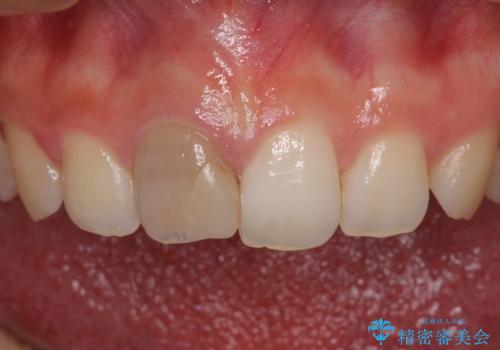

ぶつけて変色した前歯 オーダーメイドタイプのオールセラミッククラウン

- 中学生の時にぶつけて神経を取り除いた前歯の変色が気になるとのことで来院された患者様です。

レントゲン写真より、歯根の炎症が認められなかったため、ファイバーコアによる土台築製後、オーダーメイドタイプのオールセラミッククラウンにて補綴することとしました。